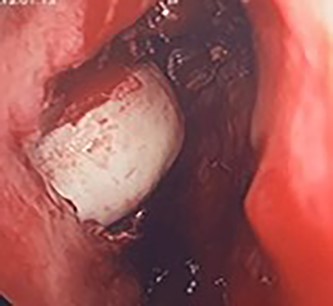

Flexible nasendoscopy offered little in terms of diagnostic benefit. An exam under anesthetic with a view to removing the ectopic tooth via endoscopic sinus surgery was warranted. Right middle turbinate trimming along with a right maxillary antrostomy was performed. The tooth was immediately identified at the antrum as depicted in Figs 4–6. The bony capsule of the tooth was entered and, on manipulation, a second ectopic tooth was identified (Fig. 7) both of which were removed en bloc. The cystic component within the maxillary sinus was marsupilized and extracted. The sinus cavity can be viewed with the utilization of 70° endoscope (Fig. 8). This facilitated bipolar cautery of the base of the cyst and confirmed the absence of an oroantral fistula.

Intra-operative image of the ectopic tooth at the right osteomeatal complex, with curved suction facilitating enucleation.